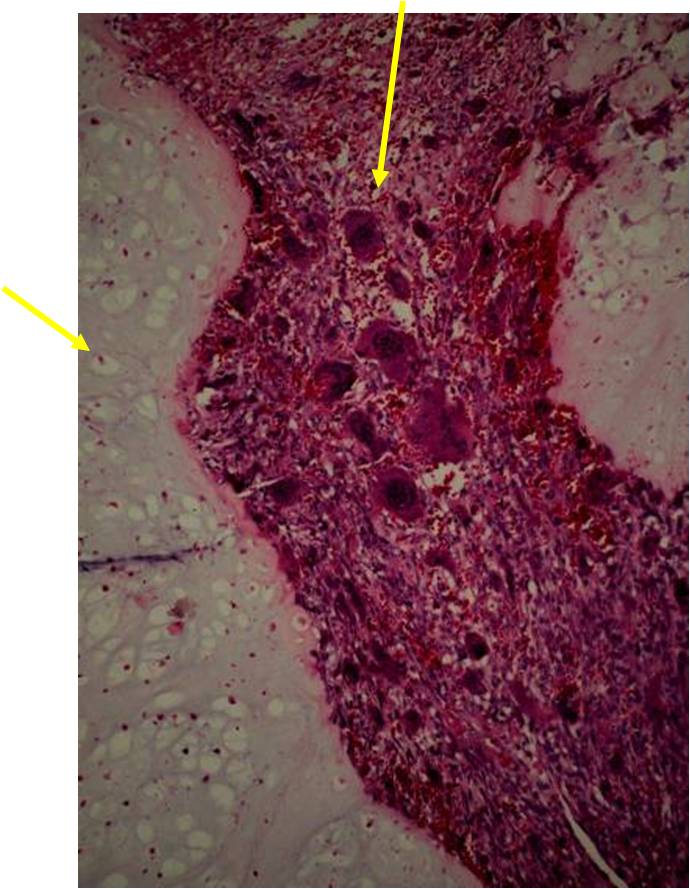

Junction of cartilaginous and noncartilaginous components is sharp and distinct. There are no dedifferentiated areas admixed in the middle of the cartilaginous areas

(Top Arrow) High Grade Dedifferentiated Spindle Cell Sarcoma Component

(Left Arrow) Low Grade Cartilage Component